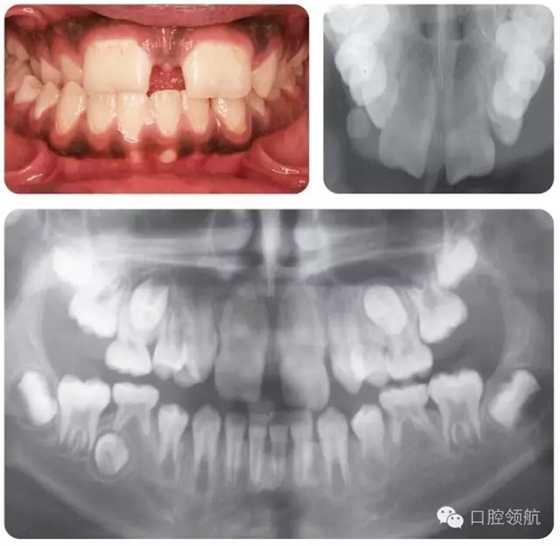

圖2.12中該名15歲男性患者的牙列特征有哪些?

圖2.12

● 上頜中切牙和側(cè)切牙為融合牙。

● LL5缺失。

● UL5,UR5和LR5阻生。

● LLE,ULE和LRE滯留。

● 尖牙和前磨牙的牙根發(fā)育滯后。

圖2.14中的牙齒情況如何?

圖2.14

磨牙切牙礦化不全(MIH)——表現(xiàn)為區(qū)域性的釉質(zhì)實(shí)質(zhì)缺陷,在系統(tǒng)發(fā)育時(shí)影響一顆或多顆恒磨牙,伴或不伴切牙損害。